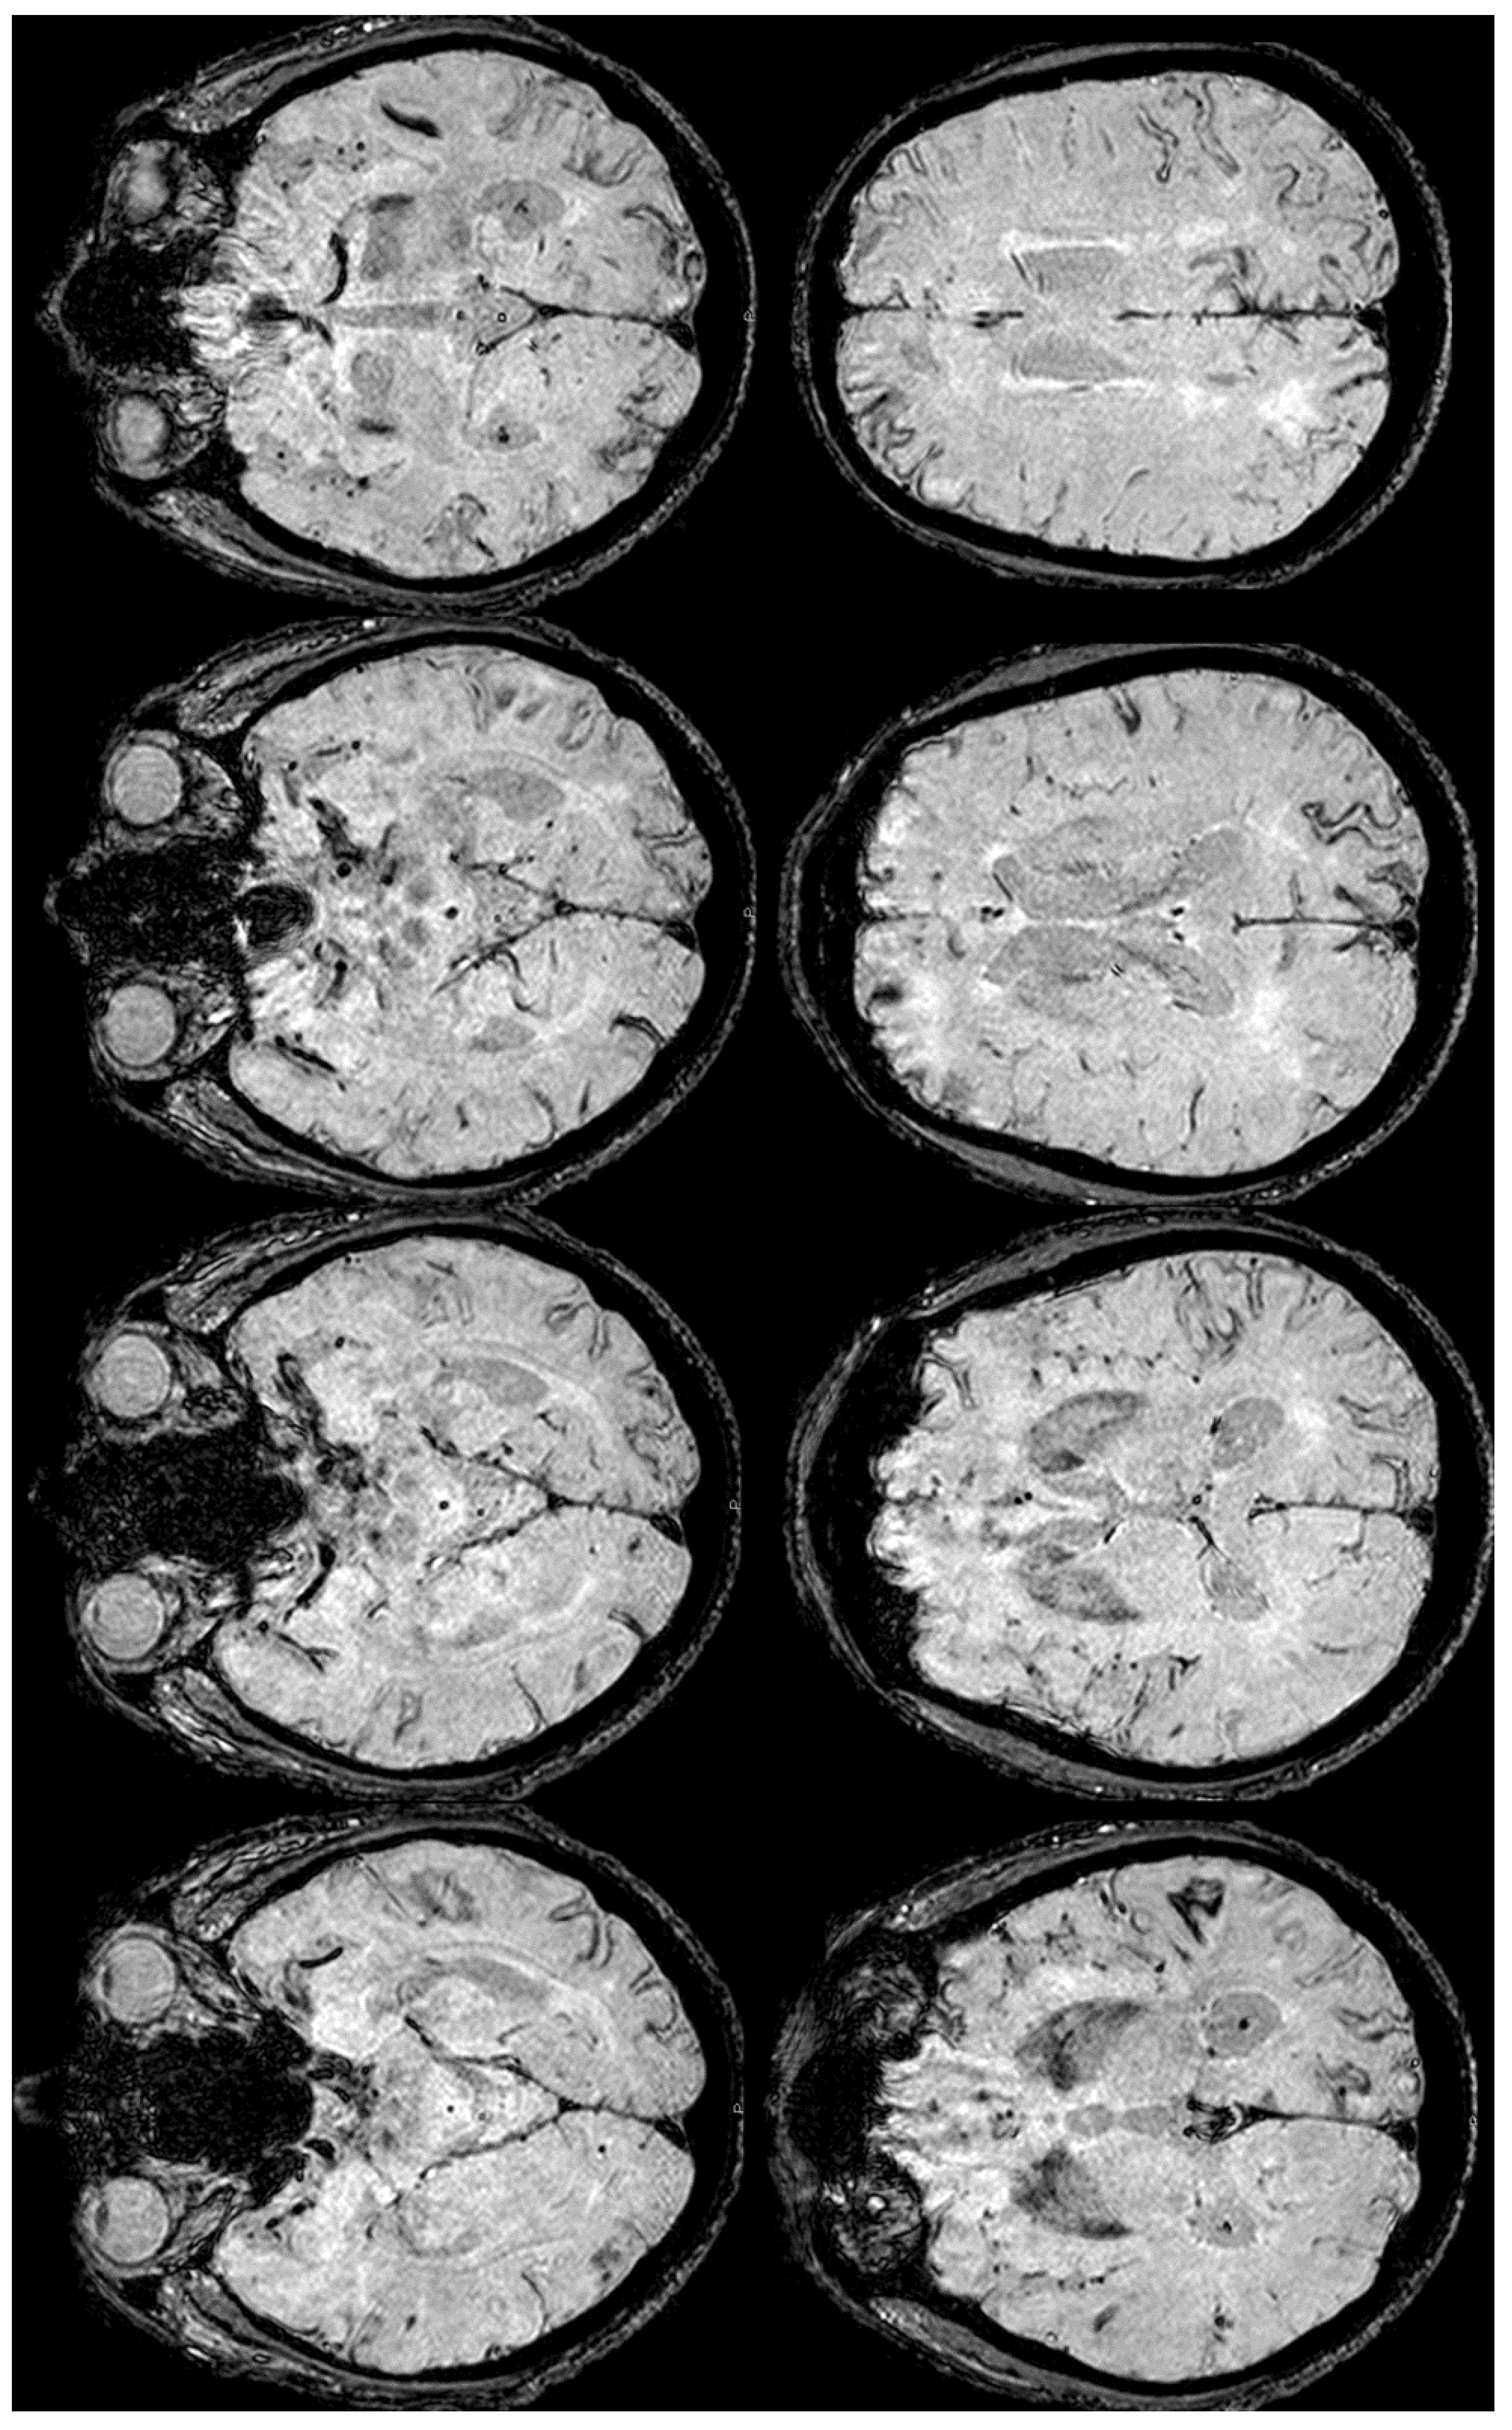

6. December 2017: Recurrent SAH